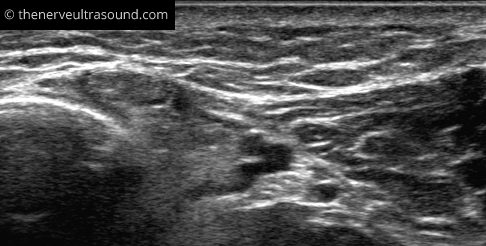

C: Distal tarsal tunnel